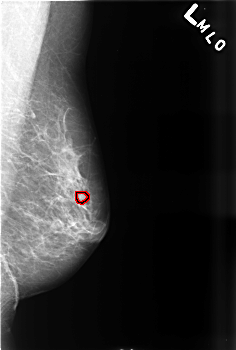

B_3471_1.LEFT_MLO

LEFT_MLO LINES 4544 PIXELS_PER_LINE 3064 BITS_PER_PIXEL 12 RESOLUTION 50 OVERLAY

FILE: B_3471_1.LEFT_MLO.OVERLAY

TOTAL_ABNORMALITIES 1

ABNORMALITY 1

LESION_TYPE CALCIFICATION TYPE PUNCTATE-PLEOMORPHIC DISTRIBUTION CLUSTERED

LESION_TYPE MASS SHAPE ROUND MARGINS MICROLOBULATED

ASSESSMENT 4

SUBTLETY 3

PATHOLOGY BENIGN

TOTAL_OUTLINES 1

BOUNDARY